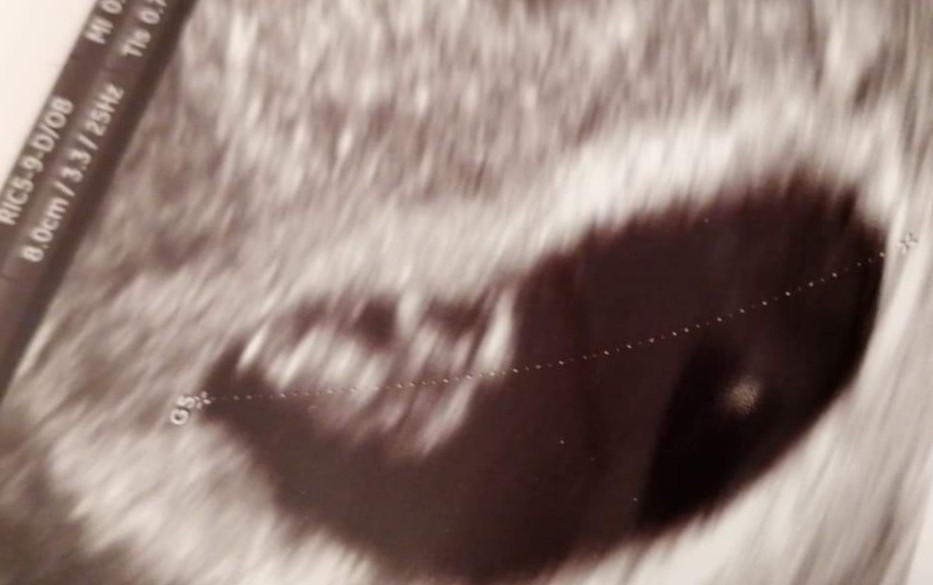

Coś takiego. Chociaż jak patrzę na zdjęcie crl zarodka to jest wpisane 7mmChyba 8mm? Bo na 6tc to chyba ni możliwe 8cm?

Wg OM to 8+0, wg usg 6+5.

Myślisz że jest ok? Bo może ja coś źle rozumiem z tego

Myślę że wszytko okeyCoś takiego. Chociaż jak patrzę na zdjęcie crl zarodka to jest wpisane 7mm

A dobra bo ja też źle napisałam. Pęcherzyk na 8 cm, maluch ma mniej. Zmęczenie, tak późno wizyty to ja nie miałamMyślę że wszytko okey![]()